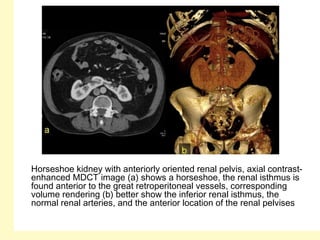

Horseshoe kidney with anteriorly oriented renal pelvis, axial contrast-

enhanced MDCT image (a) shows a horseshoe, the renal isthmus is

found anterior to the great retroperitoneal vessels, corresponding

volume rendering (b) better show the inferior renal isthmus, the

normal renal arteries, and the anterior location of the renal pelvises

I = isthmus, IMA (arrow)

Horseshoe kidney withanteriorly oriented renal pelvis, axial contrast- enhanced MDCT image (a) shows a horseshoe, the renal isthmus is found anterior to the great retroperitoneal vessels, corresponding volume rendering (b) better show the inferior renal isthmus, the normal renal arteries, and the anterior location of the renal pelvises

I = isthmus,IMA (arrow)